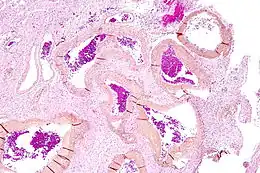

Une malformation artérioveineuse ou malformation artério-veineuse, abrégée en M.A.V, est un lien anormal entre les artères et les veines. C'est une pathologie essentiellement congénitale, mais qui peut se manifester pour la première fois assez tard dans la vie.